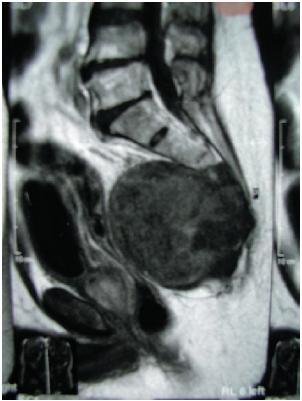

Após revisão dos prontuários, foram excluídos 21 doentes e alocados para a presente análise 15 com cordomas de topografia sacral histopatologicamente documentados. Nove doentes (60%) eram do sexo masculino e a idade variou 26 a 85, com mediana de 58 anos. Os principais sintomas foram dor (60%) e tumoração em região sacral. A tomografia computadorizada e a RNM (Figuras 1 e 2) foram diagnósticas em todos os casos.

Fig. 1 - RNM de paciente do sexo masculino, no plano sagital mediano, utilizando sequência ponderada em T1. Processo expansivo centrado em S3-S4 com crescimento anterior, bem delimitado, determinando compressão e desvio ventral do reto.